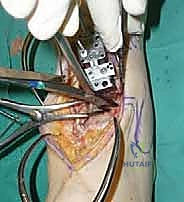

يقوم الدكتور هطيف بعمل شق طولي دقيق في الجزء الأمامي من الكاحل، طوله حوالي 10-15 سم. يتم تشريح الأنسجة بعناية فائقة للوصول إلى المفصل.

* الحماية العصبية الوعائية: هذه هي الخطوة الأكثر حرجاً. يتم تحديد الحزمة الوعائية العصبية (الشريان الظنبوبي الأمامي والعصب الشظوي العميق) وسحبها برفق شديد لحمايتها من أي ضرر جراحي.